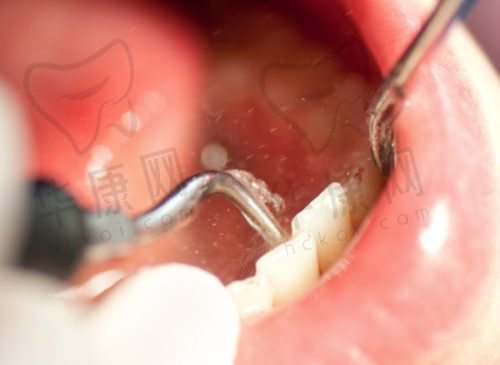

沈阳牙元素口腔推出前牙单颗根管治疗361元起的优惠活动,吸引了众多患者的关注。在沈阳,根管治疗费用因多种因素而有所不同,此次牙元素口腔的低价活动为有需求的人提供了新选择。

在沈阳地区,单颗牙齿的根管治疗费用通常在800 - 3000元之间。前牙治疗相对简单,费用一般在800 - 1500元,而后牙因根管结构复杂,费用较高,在1500 - 3000元。若需显微镜辅助或复杂修复,费用还会进一步增加。然而,沈阳牙元素口腔前牙单颗根管治疗361元起,这一价格远远低于市场平均水平。

虽然文中未详细提及医生的具体信息,但从医院的整体特色可以推测,医生团队具备专精的技能和丰富的经验。根管治疗是一项对技术要求较高的治疗项目,需要医生精细操作。